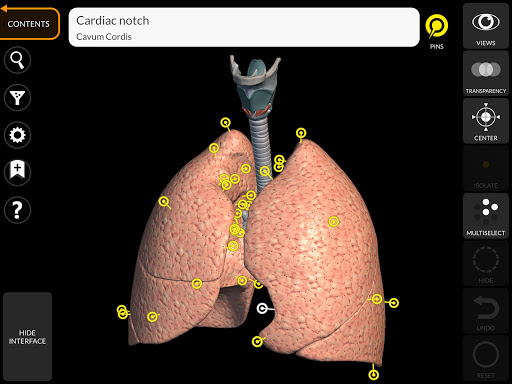

"Anatomy 3D Atlas" дозволяє легко та інтерактивно вивчати анатомію людини.

Завдяки простому та інтуїтивно зрозумілому інтерфейсу можна спостерігати кожну анатомічну структуру під будь-яким кутом.

Анатомічні 3D-моделі особливо деталізовані та мають текстури з роздільною здатністю до 4k.

• Дихальна система

• Вибравши модель або шпильку, з’явиться відповідний анатомічний термін

• Анатомічні терміни можуть відображатися двома мовами одночасно.